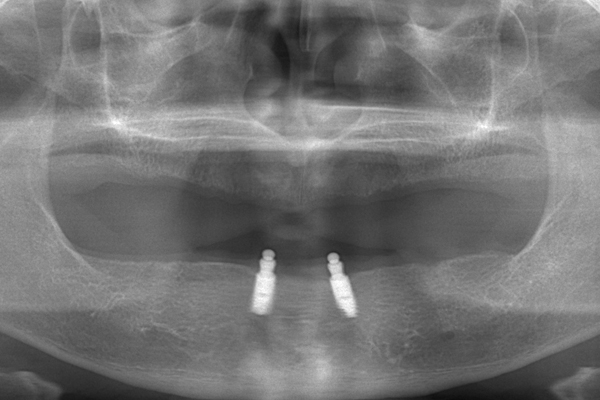

入れ歯を支える土台を埋め込みます。

インプラントが入った状態

下の義歯は2本、上の義歯には4本必要になります。